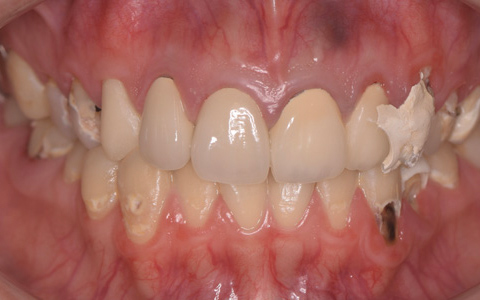

治療前

治療後

なるべく歯を残して、歯の神経も可能な限り保存し残していく方向で治療方法を検討しました。むし歯が大きく神経が侵されている歯は、抜髄を行い、精密根管治療の後にセラミックスクラウンを被せる治療方法を策定しました。患者さんのご希望と了解を得て治療を開始しました。

むし歯治療では、丁寧にむし歯だけを除去して健全な歯質だけを残します。名取歯科医院では、ラバーダムとマイクロスコープの使用が標準です。歯の根と神経の治療(根管治療)も行っていきます。

ラバーダムとはゴム製のシートで、治療する歯だけを露出させるように丁寧に切り取り、お口に装着します。唾液の中には天文学的な数の細菌が存在するため、一度治療した歯が再び悪化して再治療とならないためには、ラバーダムを装着し唾液や細菌に触れないように防湿を施した環境で治療することが何よりも大切で、歯科治療の基本です。歯の根元の黒い部分は膿の溜まった袋です。

むし歯が進行することで歯の神経まで細菌に侵されてしまった場合、昭和型の歯科治療では歯を抜いてしまう抜歯が当たり前でした。しかし、歯を抜いてしまうことで歯並びの乱れなど、ほかの歯への大きな影響があります。そこで自分の歯をできるだけ残すことを考えた「根管治療」や「保存治療」が選択されるようになってきました。

治療後の写真です。きちんと歯の根の治療(根管治療)を施すことで膿の袋も消失します。

歯ぐき(歯肉)の治療も大切です。歯ぐきを健康的な状態に治療していくことで、お口全体を審美的に優れた美しい状態に改善できます。このように歯ぐき(歯肉)の治療を行うことで、炎症を抑え、健康な状態をつくることができます。歯ぐきのコンディションを回復させると同時に、仮歯を入れます。しかしこれは治療中の隙間を埋めたり見た目を取り繕う「仮歯」とは異なります。プロビジョナルレストレーションと言い、最終的な歯(本歯)と同じ形体をもつ歯で、治療した歯や周囲の歯、反対側の歯、歯ぐきなどお口全体の回復と調和を整える大切な治療プロセスです。もちろんこの期間に仮歯での噛み合わせ、咀嚼や嚥下、または発音や発語など機能的な回復に不具合がないか、顎関節への影響や負担がないか検証する期間でもあります。

仮歯で機能回復の確認を行い、そしてさらに微調整を行います。機能的・審美的に改善を確認できた仮歯の形態を元にセラミックスクラウンを作製します。熟練した歯科技工士によるセラミックス制作を行い、装着後に最終的な微調整(咬合調整)を施し、むし歯治療、歯の根の神経治療(根管治療)、白いセラミックスによる修復治療のすべてが終了しました。

| 費用 | ジルコニアセラミック24本:5,280,000円 根管治療(小臼歯5本):770,000円 根管治療(前歯6本):792,000円 合計:6,842,000円 |

| リスク・副作用 | 治療中に一時的な咬合痛や冷温水痛、若干の歯肉の腫れ、発赤などを生じることがあります。また仮歯の時期には仮歯の脱離や破損の可能性、舌感などに違和感を覚えることがありますが、本歯に移行するまでに通常消失します。 ※すべて症例による違いや個人差があります。 |

※表示金額は全て税込みです。